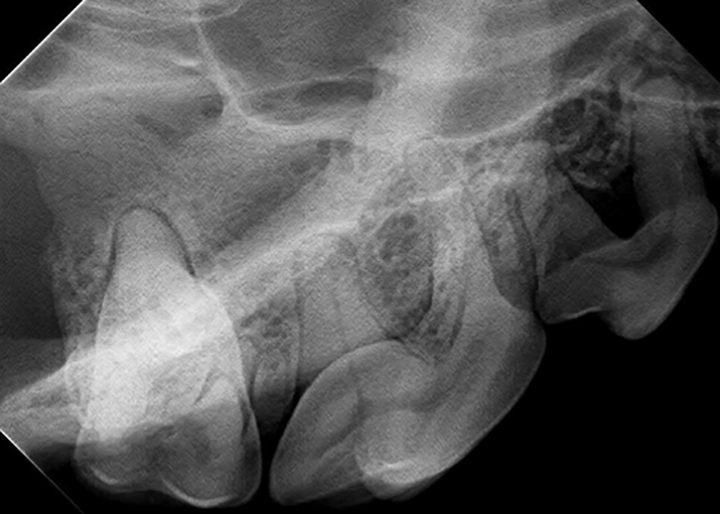

Dental XRay Positioning Guide Feline Mandibular Molars and Premolars Dental Xray Positioning the patient should be positioned: *think of dental radiographs as a “shadow” of the root of the tooth* *you need the sensor to “catch” the shadow*. the following pictures show film placement, starting position of the beam and appropriate tipping of the beam to image the five different areas of the. In order to obtain diagnostically useful images,. Dental Xray Positioning.

From davidxray.com